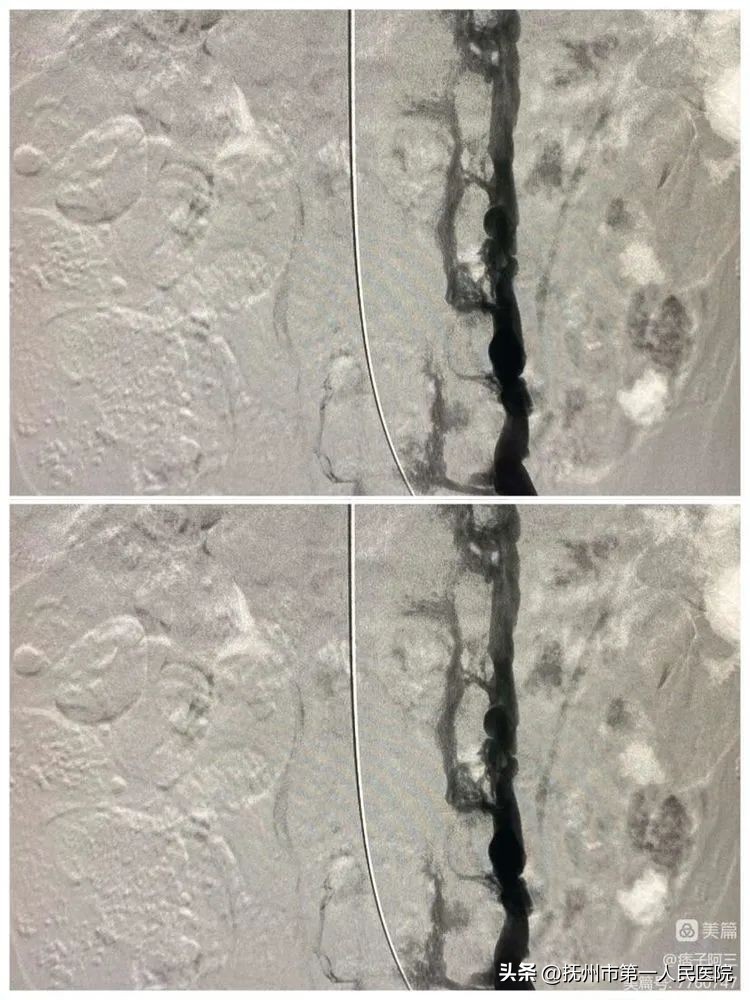

为了尽快给患者早期治疗指明方向、胡伟在导管室数字减影血管造影机的引导和监视下,为患者实施下腔静脉造影。通过血管造影,最后明确诊断为:复杂性布加氏综合症(下腔静脉阻塞型)。

术中再次造影、明确具体狭窄情况